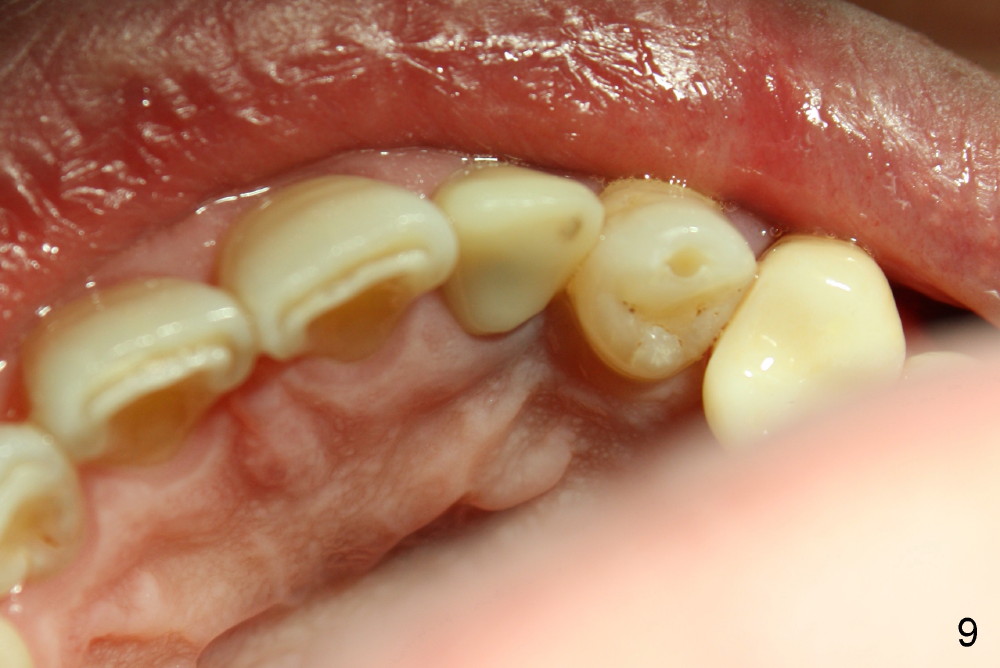

5. Crown form for temporary, intentionally off occlusion

6. Provisional keeps papillae in place